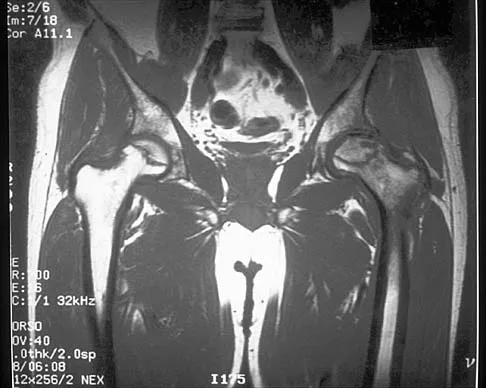

Figure 41 shows the MRI scan of a 39-year-old man who has severe left groin and anterior thigh pain. What is the most likely diagnosis?